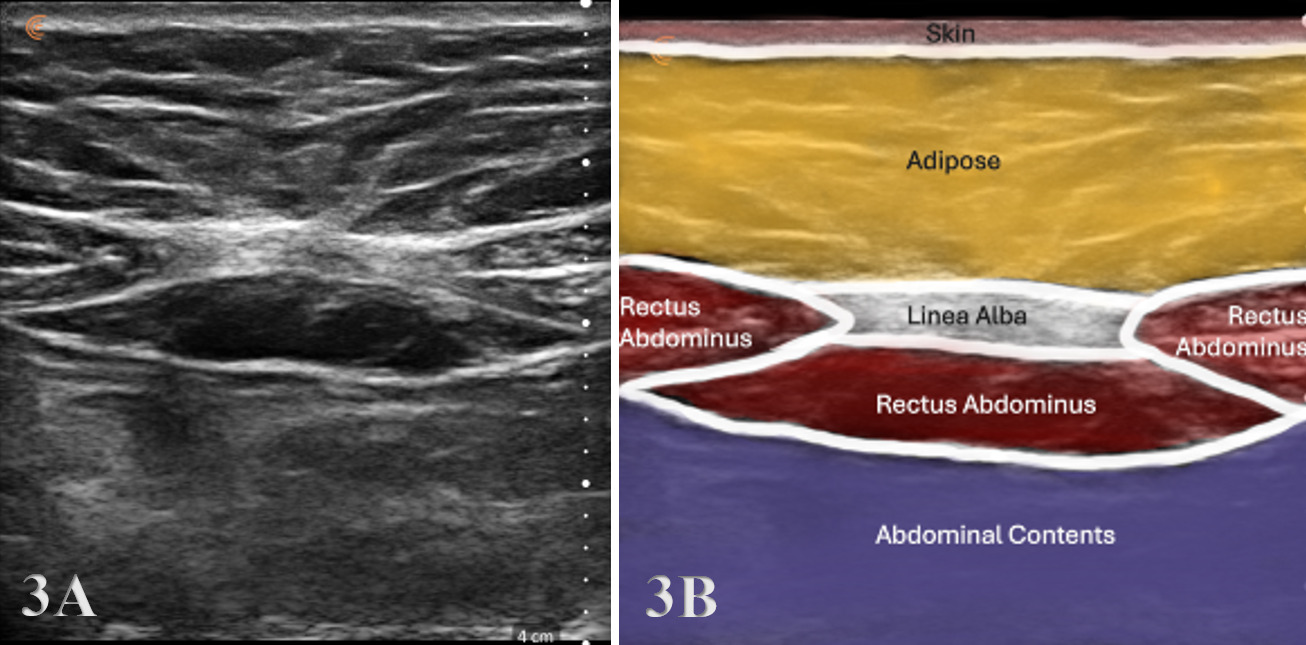

Typically, the transducer will be placed near the proximal portion of the RA perpendicular to the muscle fibers in the SAX. In this position, the transducer can be moved both proximally and distally and can examine the RA in the transverse plane. The cross-section of the RA will be seen as fibular hypoechoic muscle tissue. Additionally, the examiner should be able to easily discern the hyperechoic linea alba and rectus sheath.

To obtain a SAX view, rotate the transducer 90° with the marker toward the patient’s right and center over the LA at the chosen level (−2/0/+2 cm relative to the umbilicus). Identify the echogenic linea alba midline, paired RA bellies on either side, and their sheaths.